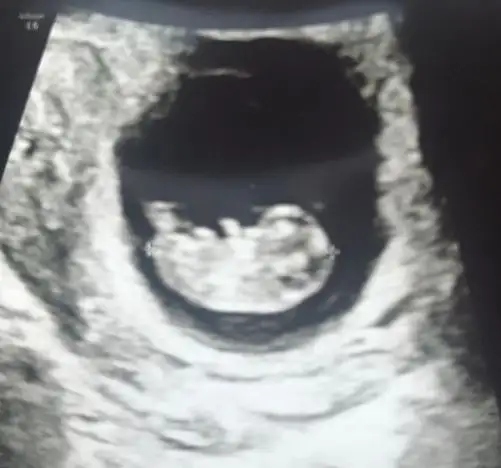

Merhaba kizlar normalde 7+4 olmam lazim ultrasonda 6+4 ciktim sizce konuma gore cinsiyti ne bana cok ortada geldi sanki karar veremedim